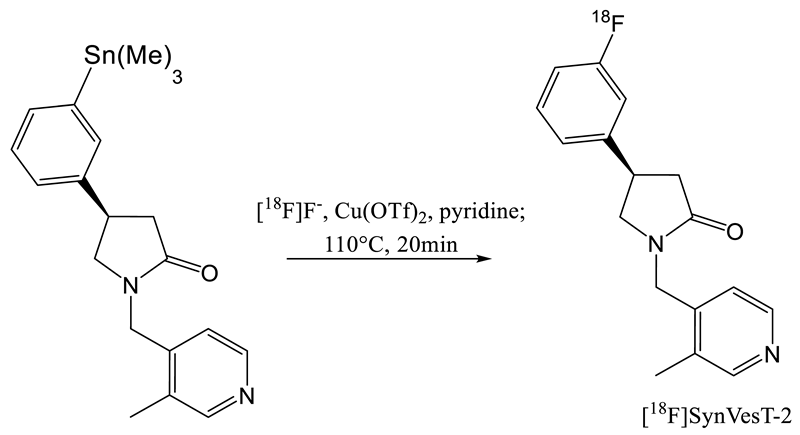

2. Radiochemistry of SV2A PET Radiotracers

- Cai, Z.; Li, S.; Zhang, W.; Pracitto, R.; Wu, X.; Baum, E.; Finnema, S.J.; Holden, D.; Toyonaga, T.; Lin, S.-F.; et al. Synthesis and Preclinical Evaluation of an 18F-Labeled Synaptic Vesicle Glycoprotein 2A PET Imaging Probe: [18F]SynVesT-2. ACS Chem. Neurosci. 2020, 11, 592–603. [Google Scholar] [CrossRef] [PubMed]

- Patel, S.; Knight, A.; Krause, S.; Teceno, T.; Tresse, C.; Li, S.; Cai, Z.; Gouasmat, A.; Carroll, V.M.; Barret, O.; et al. Preclinical In Vitro and In Vivo Characterization of Synaptic Vesicle 2A-Targeting Compounds Amenable to F-18 Labeling as Potential PET Radioligands for Imaging of Synapse Integrity. Mol. Imaging Biol. 2019, 1–10. [Google Scholar] [CrossRef] [PubMed]

| Entry | Tracer | Ref | Synthesis of the Radiotracer | pIC50 for Human SV2A | Ki (nM) for Human SV2A | Molar Activity (GBq. µmol−1) | RCY (%) |

|---|---|---|---|---|---|---|---|

| 1 | [11C]Levetir-acetam | [18] |  | 5.7 [24] | 2500 | 17 | 8.3 (dc) |

| 2 | [18F]UCB-H | [19] |  | 7.8 | 9.0 | 518 | 15 (ndc) |

| 3 | [21] |  | 815 ± 185 | 35 (ndc) | |||

| 4 | [18F]UCB-A | [23] |  | 7.9 [24] | ND a | 65 | 14 (dc) |

| 5 | [11C]UCB-J | [24] |  | 8.2 | 1.5 | 215 | 35 (dc) |

| 6 | [18F]UCB-J | [27] |  | Similar to [11C]UCB-J | Similar to [11C]UCB-J | 59 ± 36 | 1–2 (ndc) |

| 7 | [18F]SynVesT-1 | [28,29] |  | 8.4 | 2.2–4.7 b | 242 | 19 (ndc) |

| 8 | [18F]SynVesT-2 | [31] |  | ND a | 12 | 141 | 7(dc) |

| 9 | [18F]1 | [33] |  | 8.3 | ND a | 40–80 | 1.5 (dc) |